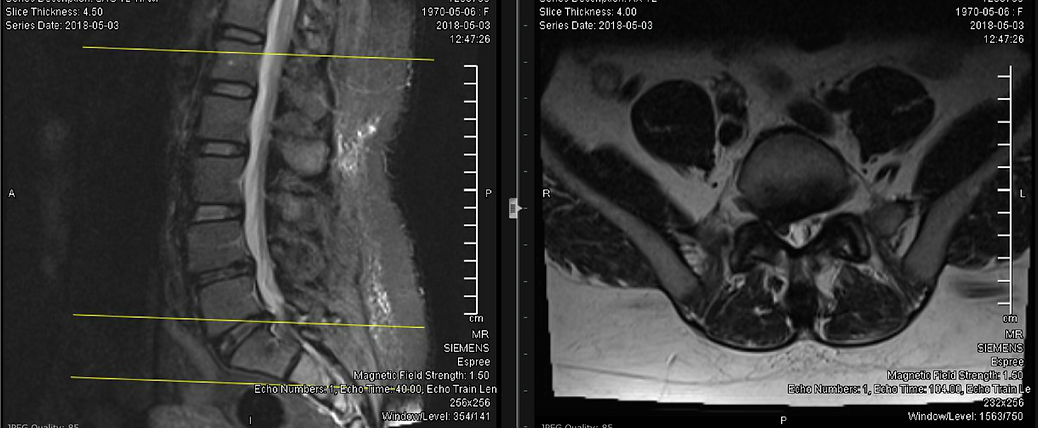

- Obtain a new MRI of the lumbar spine